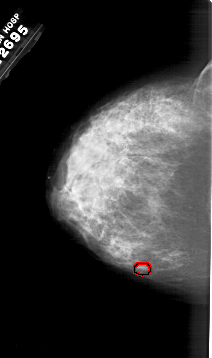

A_1983_1.RIGHT_CC

RIGHT_CC LINES 6481 PIXELS_PER_LINE 3856 BITS_PER_PIXEL 12 RESOLUTION 43.5 NON_OVERLAY

FILE: A_1983_1.LEFT_MLO.OVERLAY

TOTAL_ABNORMALITIES 1

ABNORMALITY 1

LESION_TYPE CALCIFICATION TYPE PUNCTATE DISTRIBUTION CLUSTERED

ASSESSMENT 4

SUBTLETY 1

PATHOLOGY MALIGNANT

TOTAL_OUTLINES 1

BOUNDARY